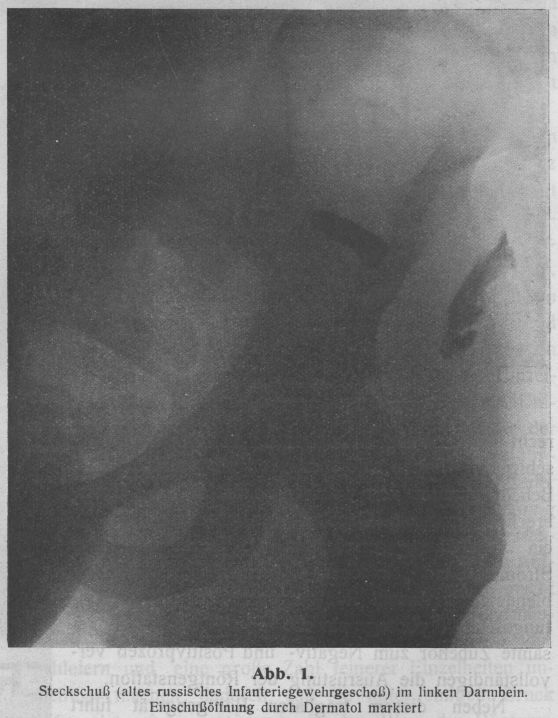

Textabbildung Bd. 330, S. 84

Abb. 9. Schußfraktur des Oberarmes durch russisches Gewehrspitzgeschoß, das

stark abgeplattet ist. Der Geschoßmantel ist aufgeplatzt und der Bleikern in

zahlreiche Stückchen zerspritzt. Starke Verschiebung der Fragmente

Abb. 10. Derselbe Fall wie Abb. 9, in Gipsverband. Dislokation noch nicht ganz

beseitigt; Geschoß operativ entfernt

Die Untersuchung mittels Röntgenstrahlen gibt nicht nur sofort ein klares Bild über

Art und Schwere der Knochenverletzungen, sie ist auch vorzüglich geeignet zur

Ueberwachung des Heilverlaufes. Dabei brauchen etwaige Gips- oder Streckverbände (s.

Abb. 9 und 10)

nicht abgenommen werden, so daß dem Kranken weder Belästigungen noch Schmerzen

entstehen, und die Heilung ohne Störung verlaufen kann.